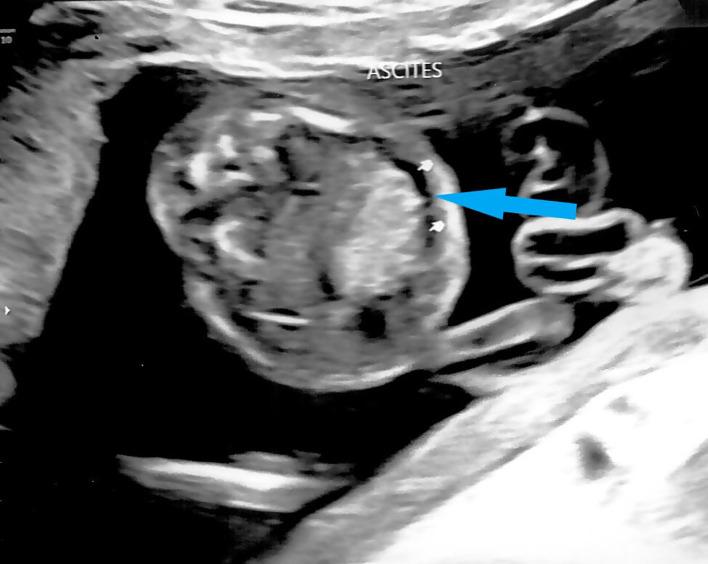

Hemoglobin (Hb) Bart's hydrops fetalis is the most severe form of α-thalassemia and is usually inherited in an autosomal recessive manner. We report a case of Hb Bart's hydrops fetalis due to uniparental disomy of chromosome 16. Antenatal screening showed a low maternal mean corpuscular volume (MCV), while paternal MCV was normal. The fetus was found to have a thickened nuchal translucency during first trimester screening for Down's syndrome. Mid-trimester fetal anomaly ultrasound scan showed fetal cardiomegaly with pericardial effusion, scalp edema, ascites and an elevated middle cerebral arterial peak systolic velocity (MCA PSV). Multiplex polymerase chain reaction (PCR) on DNA from amniocentesis showed that the fetus was homozygous for South East Asian (SEA) type 2 α-globin gene deletion. Chromosome microarray (CMA) showed two regions of absence of heterozygosity (AOH) on the terminal p and q arm of chromosome 16. The rare occurrence of Hb Bart's hydrops fetalis caused by maternal uniparental disomy should be considered in cases of fetal hydrops even in cases where paternal MCV is normal.

血红蛋白(Hb)巴特胎儿水肿综合征是α地中海贫血最严重的形式,通常以常染色体隐性方式遗传。我们报告了一例因16号染色体单亲二体导致的血红蛋白巴特胎儿水肿综合征病例。产前筛查显示母亲平均红细胞体积(MCV)较低,而父亲的MCV正常。在孕早期唐氏综合征筛查中,发现胎儿颈部半透明层增厚。孕中期胎儿畸形超声扫描显示胎儿心脏肥大并伴有心包积液、头皮水肿、腹水以及大脑中动脉收缩期峰值流速(MCA PSV)升高。对羊水穿刺获得的DNA进行多重聚合酶链反应(PCR)显示,胎儿为东南亚(SEA)型2α珠蛋白基因缺失纯合子。染色体微阵列(CMA)显示16号染色体末端p和q臂上有两个杂合性缺失(AOH)区域。即使父亲的MCV正常,在胎儿水肿的病例中也应考虑由母亲单亲二体导致的罕见血红蛋白巴特胎儿水肿综合征。